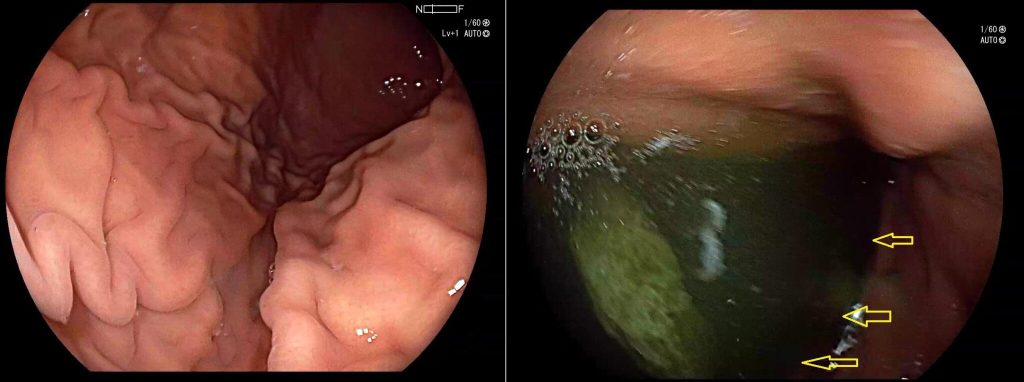

Metaplasia intestinal alrededor del píloro en el reflujo biliar duodenogástrico. Imagen de cromoendoscopia digital.

Entre las posibles complicaciones que se pueden desarrollar se encuentran:

• Desarrollo de lesiones gástricas preneoplásicas: progresión de gastritis atrófica a metaplasia intestinal y displasia que ven acelerada su evolución hacia el cáncer gástrico por la presencia de reflujo biliar.

• Úlceras gástricas.

• Alteraciones funcionales como el deterioro de la motilidad gástrica, los trastornos de la secreción ácida, la alteración de la barrera mucosa o la malabsorción de algunos nutrientes.

• Complicaciones sistémicas: Son infrecuentes, pero puedes desarrollar anemia por malabsorción, deficiencias nutricionales, o pérdida de peso.